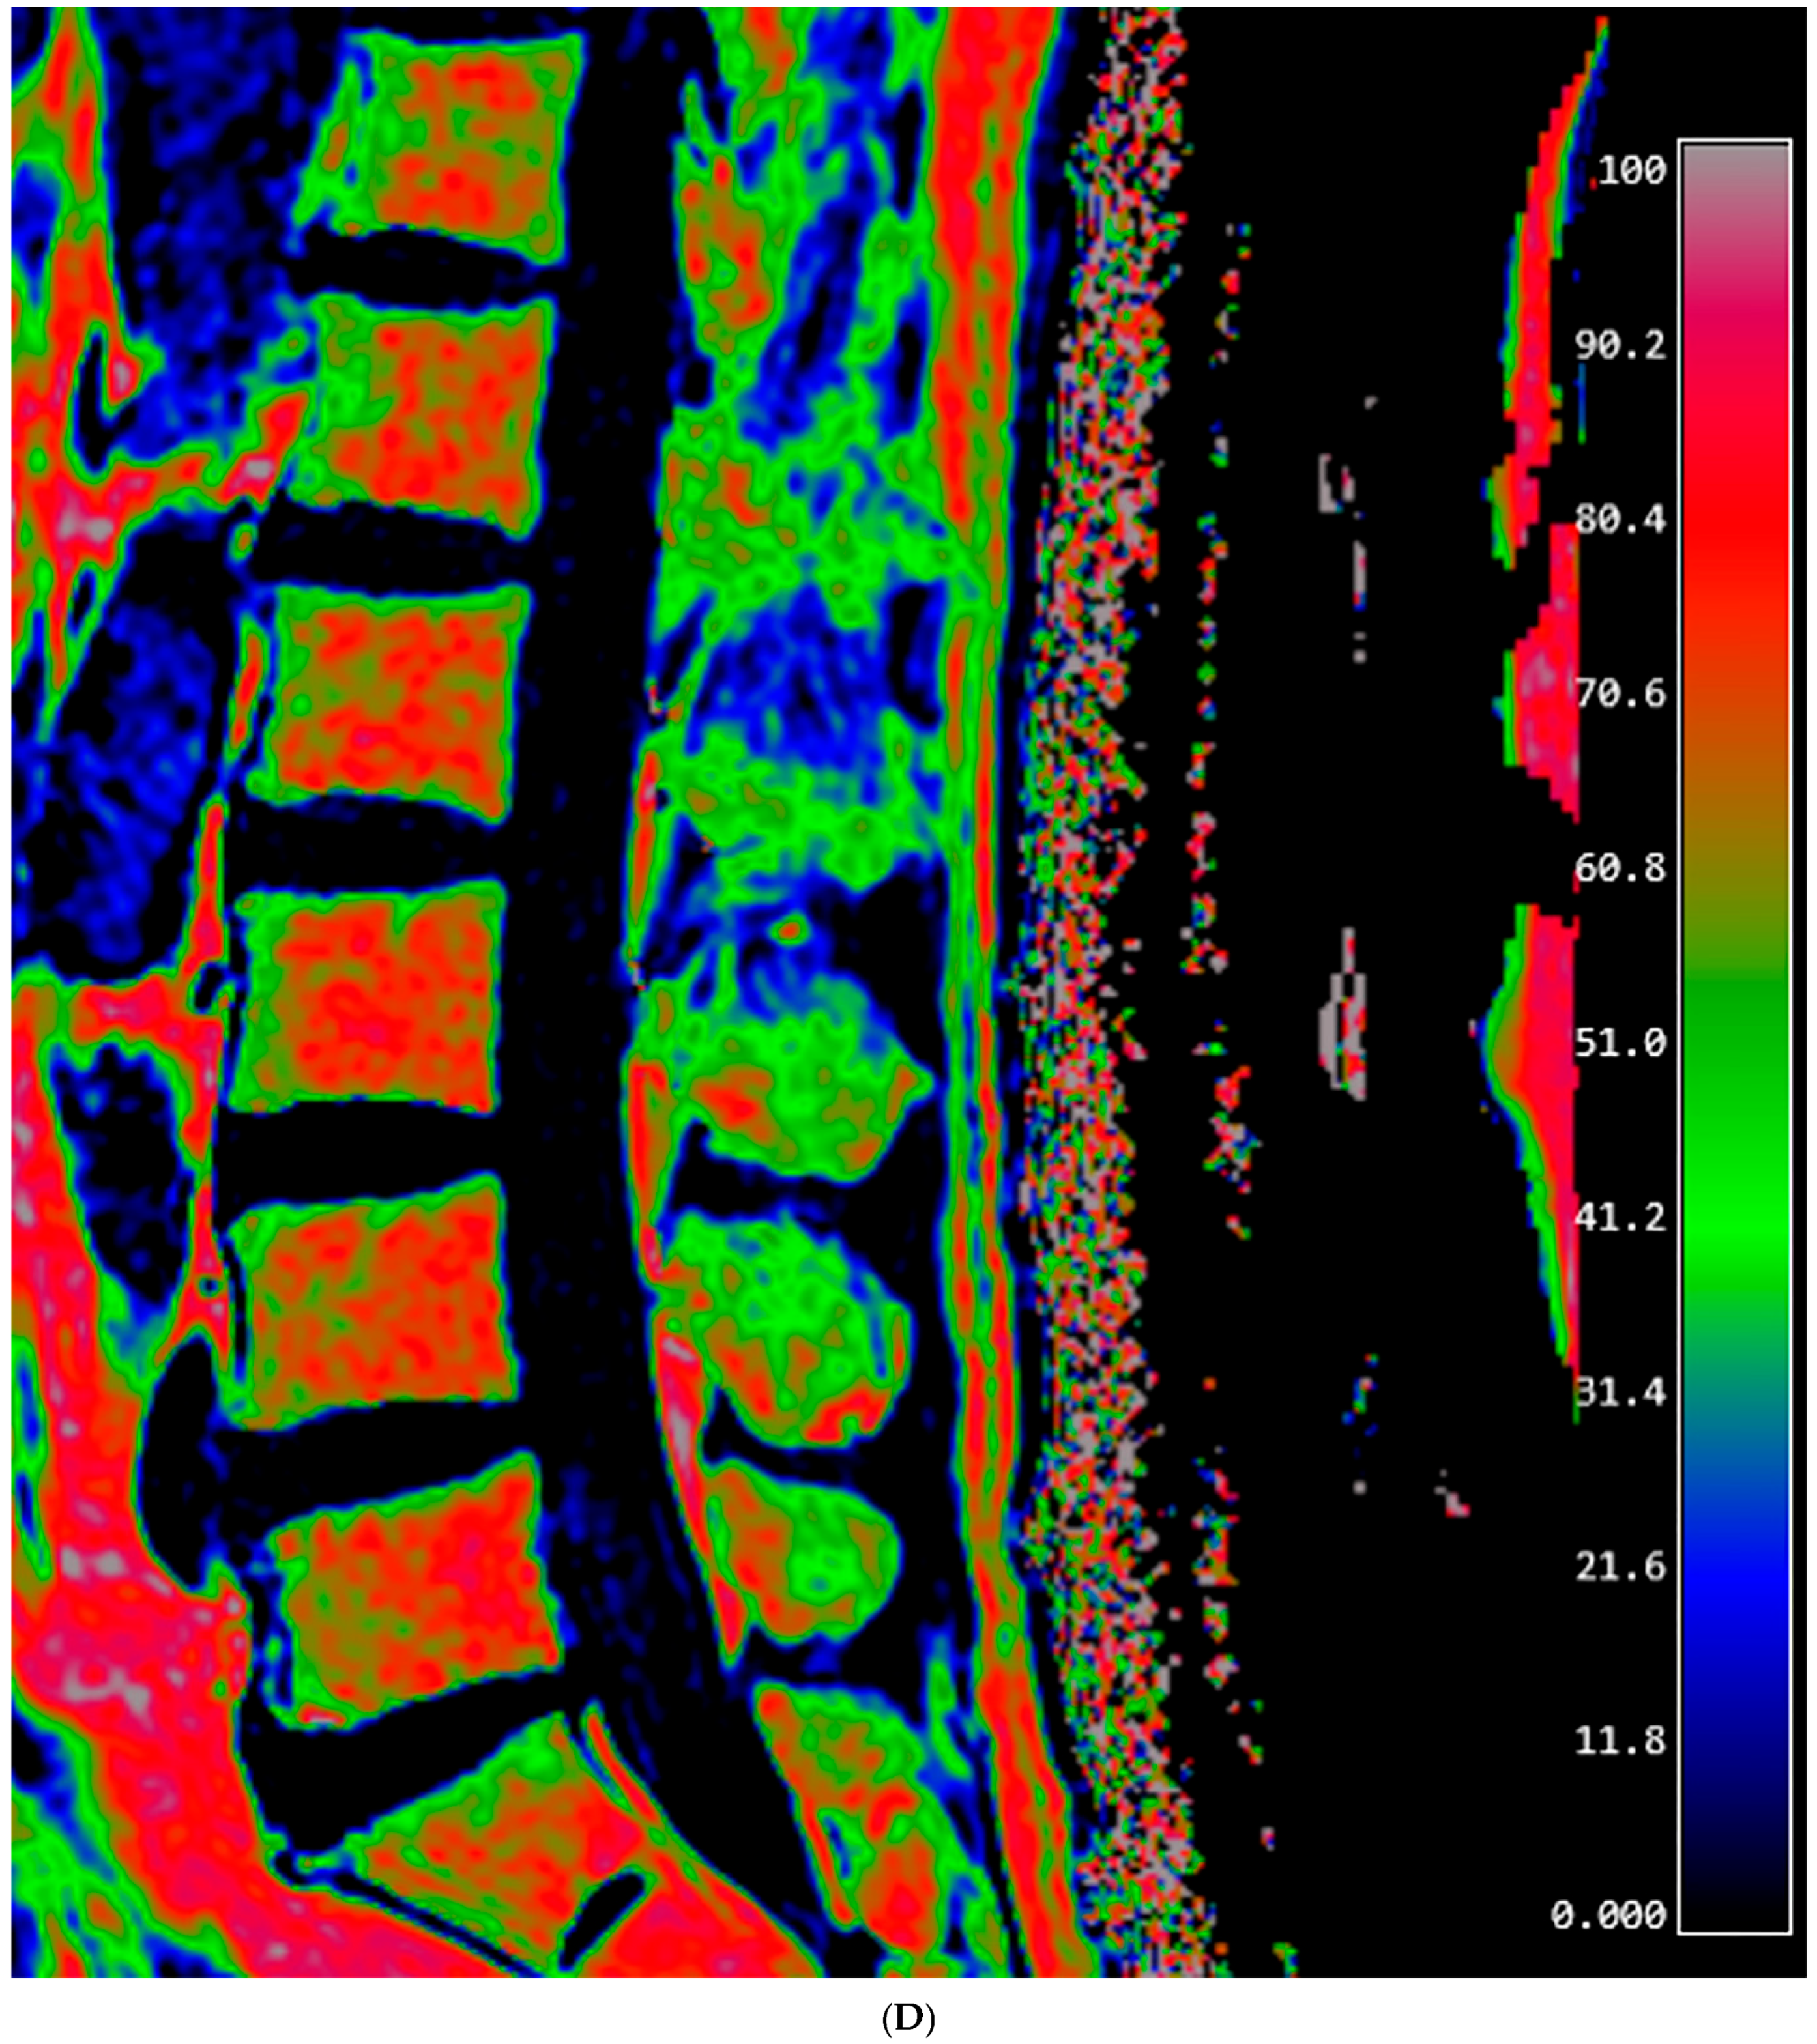

2.3. Fat Fraction Measurement